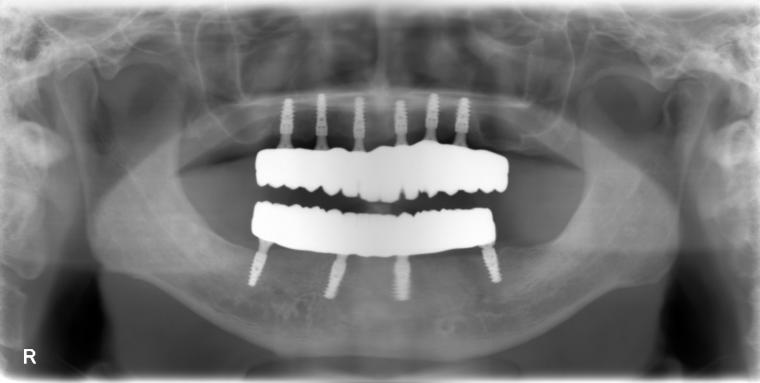

62歳男性/オールオン4・6症例/インプラント埋込手術

オールオン4・6というインプラント義歯での治療を選択されました。

義歯とは違い、外して洗浄する手間や、食事中にずれたりすることがないので、快適に使用されているそうです。